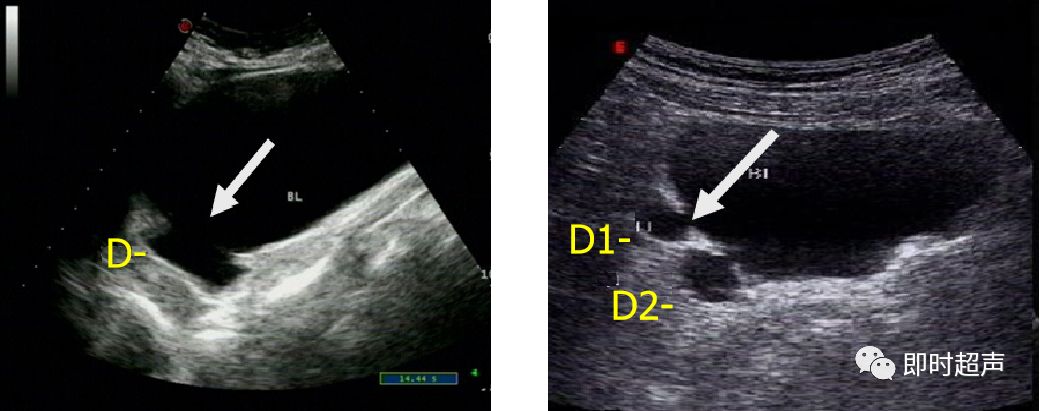

单发 多发

D:憩室 憩室口(箭头所示)